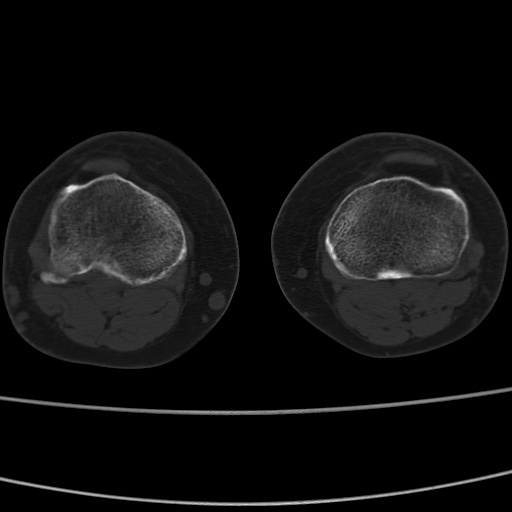

女性,50岁。【请提供患者临床症状体征】

右膝关节退行性改变,关节游离鼠。

右膝关节退行性改变,滑膜黏液囊钙/骨化并游离。

右膝关节退行性改变